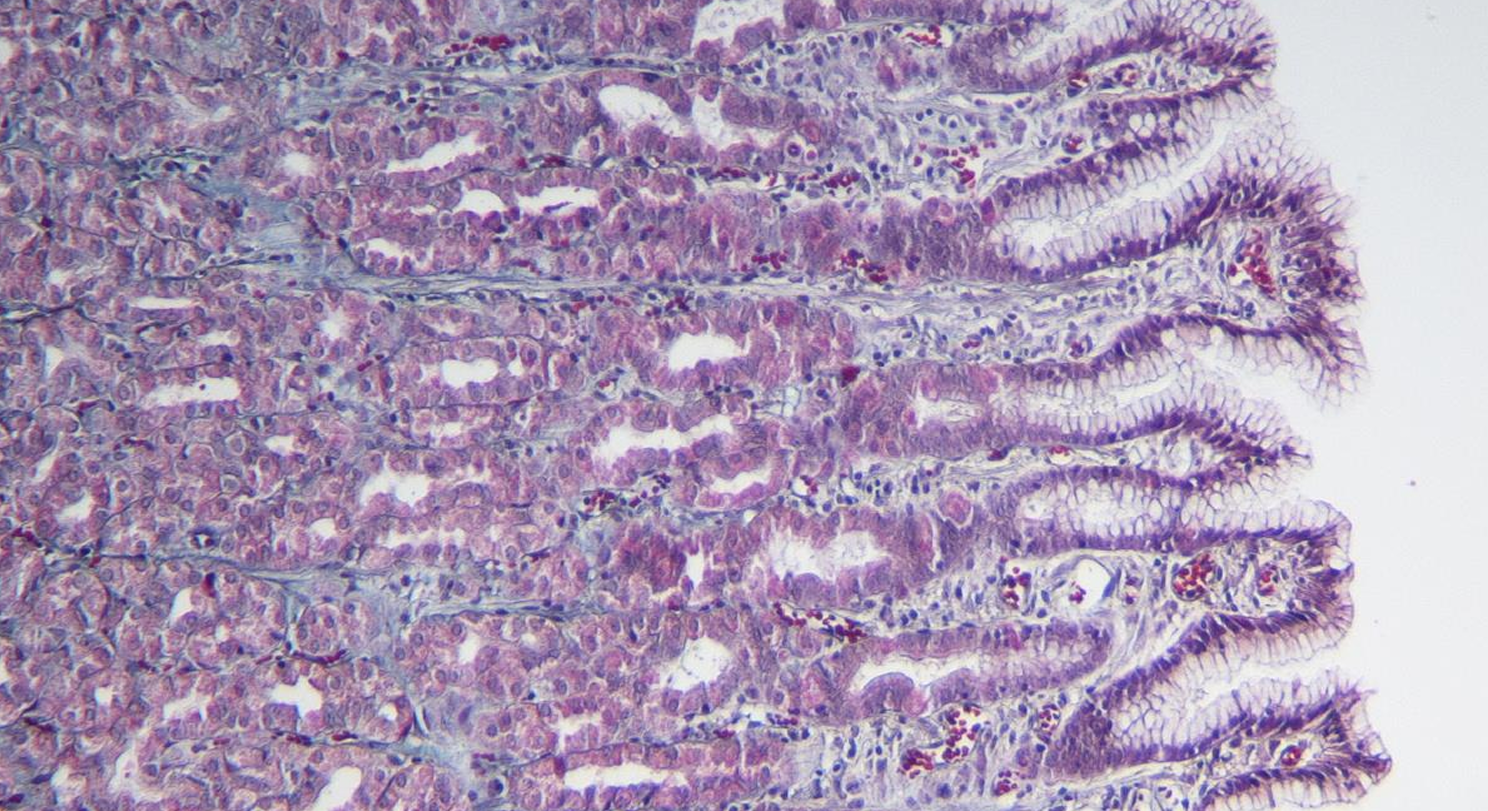

intestino grueso es la parte final del sistema digestivo, encargada de absorber agua y electrolitos, además de formar y eliminar las heces.

intestino grueso

colon